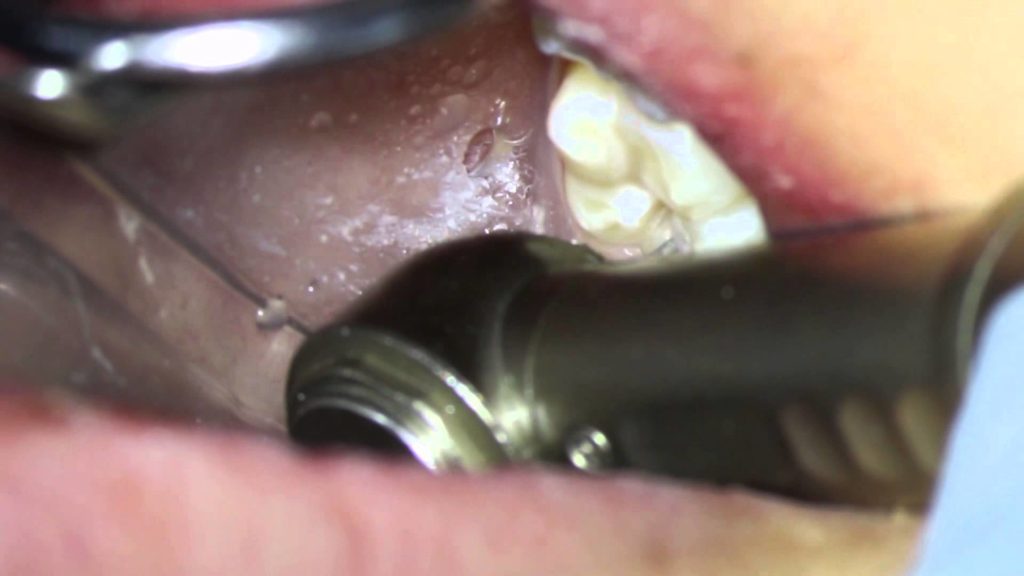

home Health Concerns Removing small cavities Removing small cavities By dentists Posted in Health Concerns Posted on May 16, 2017